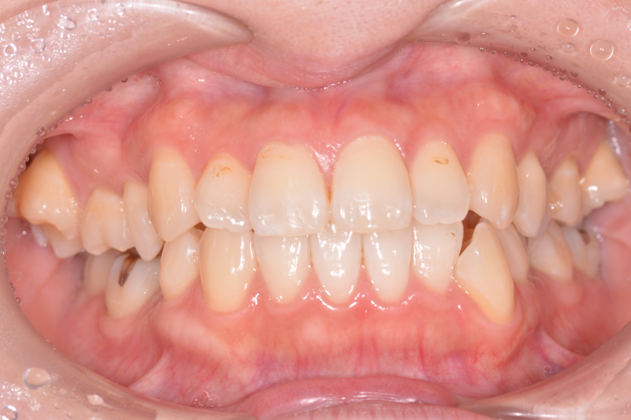

症例2

| 来院時の主訴 | 「右上の、内側に生えている歯が邪魔。」 |

| 矯正法 | 上の歯2本、下の歯2本、親知らず3本を抜歯しての矯正 |

| 通院期間 | 3年6ヶ月 |

| ここがこだわりのポイント!☝ | こちらの患者様は上の歯が1本内側に生えていましたが、奥歯の噛み合わせの方が問題でした。ハサミ状咬合といい、奥歯が極端に外側に向いており、下の歯と噛み合っていない状態でした。ハサミ状咬合は長期的にみると、前歯に大きな負担がかかったり、磨きにくい事による虫歯や歯周病になりやすいなどのリスクがあります。治療期間はかかりましたが、見た目の良さだけでなく、機能的にも改善しました。 |